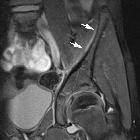

Subperiosteal

hematoma of the ilium: an unusual complication of acetabular fracture. Forty days after trauma, the subperiosteal hematoma of the right iliac bone (asterisk) is decreased in size. Within the collection, some clots can be seen (curved arrow).